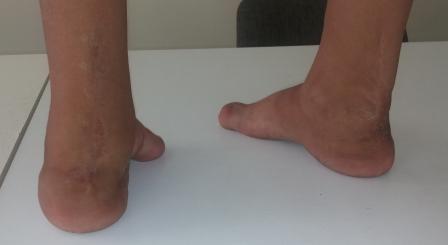

фото до лечения, после операции по Зацепину в год и операции резекции костей стопы по типу Куслика в пять лет

после 5 повязок и подкожной ахилотомии и снова гипсовой повязки на три месяца

Ребенку на фото 9 лет